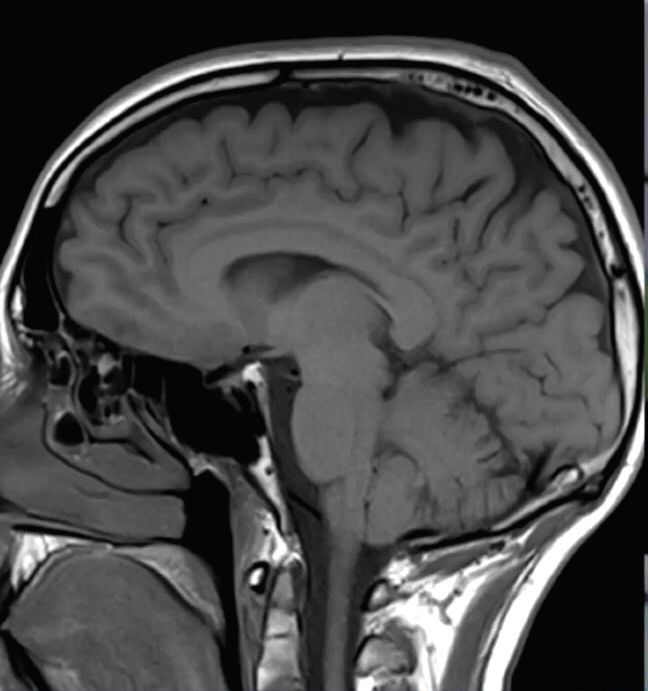

NEW YORK, JANUARY 13 (IANS): Researchers have discovered that SARS-CoV-2 can directly infect the central nervous system and have begun to unravel some of the virus's effects on brain cells.

The study, that used both mouse and human brain tissue, indicates that SARS-CoV-2 can affect many other organs in the body, including, in some patients, the central nervous system, where infection is associated with a variety of symptoms ranging from headaches and loss of taste and smell to impaired consciousness, delirium, strokes and cerebral haemorrhage.

The researchers found that the virus was able to infect neurons in these organoids and use the neuronal cell machinery to replicate. The virus appears to facilitate its replication by boosting the metabolism of infected cells, while neighbouring, uninfected neurons die as their oxygen supply is reduced.

SARS-CoV-2 was also able to infect the brains of mice genetically engineered to produce human ACE2, causing dramatic alterations in the brain's blood vessels that could potentially disrupt the organ's oxygen supply, the team said.

SARS-CoV-2 was detected in the cortical neurons of one of these patients, and the infected brain regions were associated with ischemic infarcts in which decreased blood supply causes localized tissue damage and cell death. Microinfarcts were detected in the brain autopsy of all three patients.